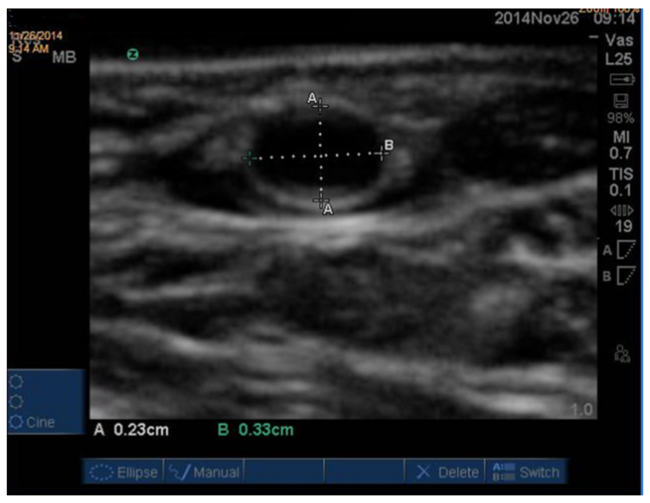

RA/UA measurements were performed using a SonoSite M Turbo portable ultrasound machine equipped with an L25 13-6 MHz vascular transducer probe (SonoSite, Inc) in 2 perpendicular axes: vertical (A, 12–6 o’clock axis) and horizontal (B, 3–9 o’clock axis) (Figure 1). Ultrasound measurements were performed at the typical needle entry points on the wrist, ie, 1-3 cm proximal to the radial styloid process or the pisiform bone. The diameters were measured from the inner-to-inner border of the arterial wall, ie, media to media. The effective size of the artery was calculated as: (A+B)/2.